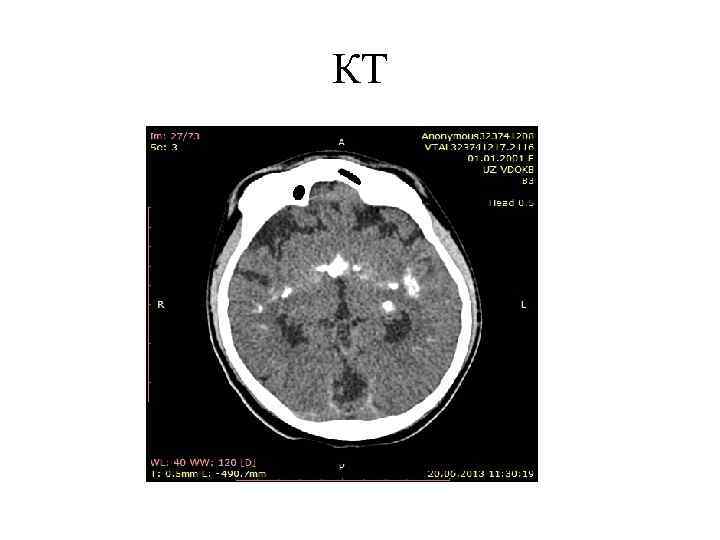

КТ - определяется расширение ликворосодержащих пространств (симметричная или асимметричная вентрикуломегалия), расширение субарахноидальных пространств. Для обструктивных форм характерно снижение плотности в перивентрикулярных областях. Для сообщающейся гидроцефалии характерно умеренное расширение ликворосодержащих пространств и признаки корковой и центральной атрофии.

кт